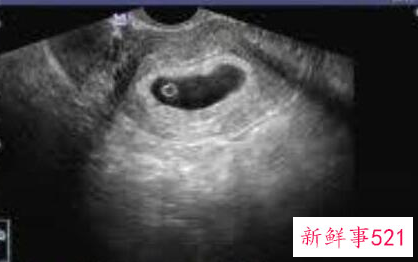

【孕囊】怀孕7-9周会做第一个b超,确定是否宫内以及胎压胎心,这一点大家很熟悉了。分辨方法是圆圆的孕囊代表的是女孩,长条形的、椭圆形的代表是男孩。

10、长型孕囊为男孩,圆型孕囊为女孩

说明:男孩子在怀孕两个月前的孕囊是长型的,女孩子是椭圆或是圆型。准妈妈们的孕囊看上去形状有所区别与胎儿性别没有关系。孕囊的形状由张力和含羊水量决定的,会自行改变形状。这样,怀孕天数不同,看到的孕囊也可能不一样。另外,每次B 超探头的方向不同,从不同的角度看,孕囊的形状也是不一样的。